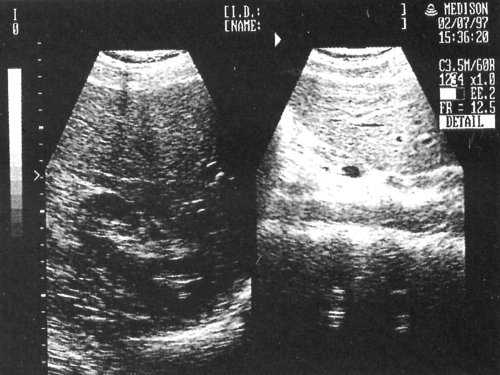

При гиперспленизме отмечают уменьшение количества эритроцитов, нейтрофилов или тромбоцитов в мазках периферической крови. Диагноз «гемолиз», связанный с ускорением оборота эритроцитов, предполагают при ретикулоцитозе и повышении концентрации общего и непрямого билирубина в сыворотке крови.![Спленомегалия]()

Рис. 17.1. Спленомегалия: а — в левой половине живота очерчены контуры пальпируемой селезенки; б — увеличение размеров печени и селезенки при гепатоспленсцинтиграфии